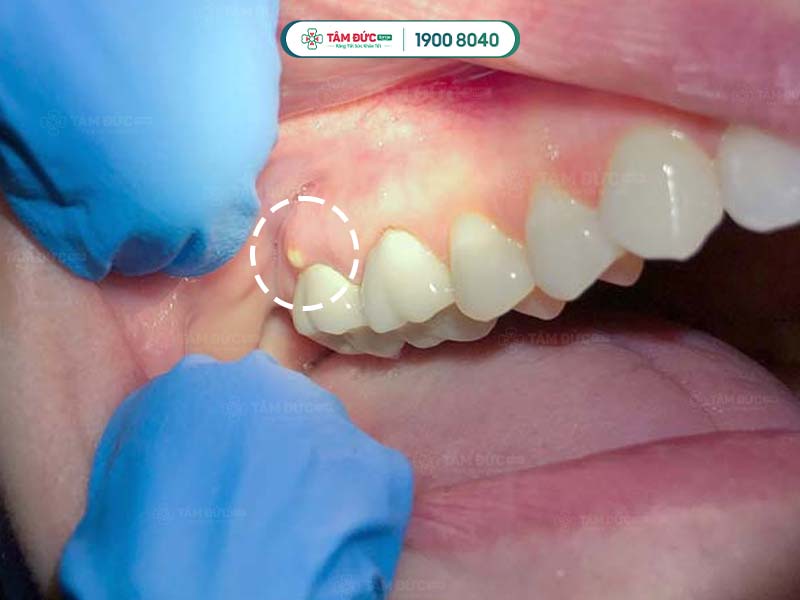

Nướu răng hàm trên bị sưng và tụ mủ

Viêm nướu làm sưng viêm và có mủ

- Áp xe răng: Đây là bệnh nhiễm trùng nghiêm trọng ở chân răng, có thể gây sưng, đỏ, đau nhức dữ dội, sốt, thậm chí là sưng mặt.